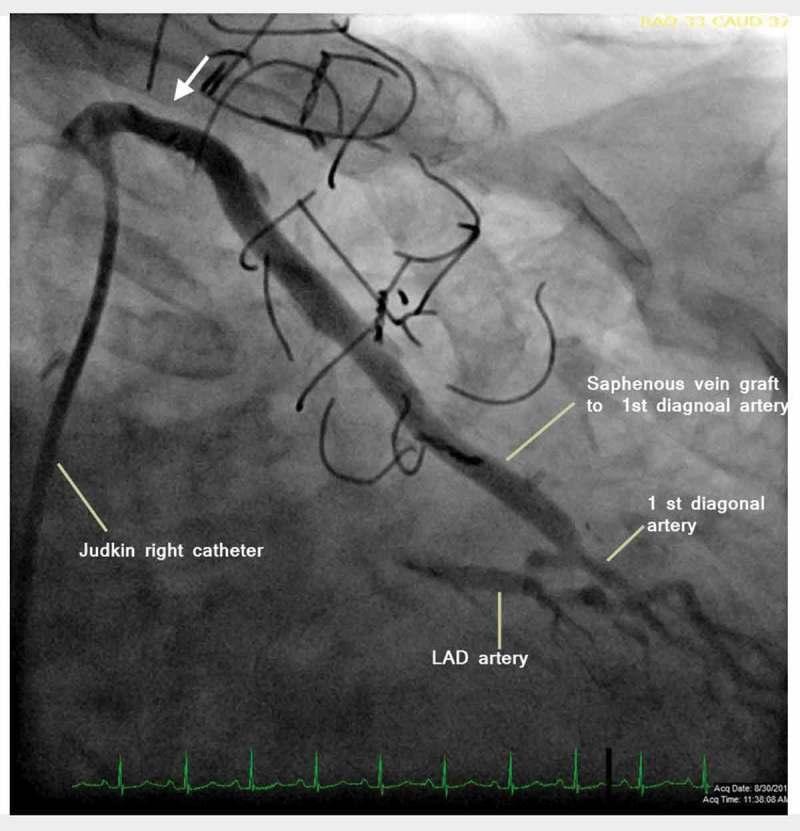

Spasm following coronary artery bypass graft surgery has been well established in arterial grafts, especially in grafts utilizing the internal mammary. Venous graft spasms are uncommon and are only observed in vein grafts during or soon after the coronary artery bypass surgery. It is exceedingly rare to see spasm of venous graft beyond one year of surgery. We report a 72-year-old female who had coronary artery bypass graft three years ago and presented with new onset chest pain for one month. The coronary angiogram revealed severe spasm of the proximal aspect of a patent saphenous venous graft which was relieved by intracoronary nitroglycerine. Patient was successfully managed using combination of anti-spasmodic medications (nitrates and calcium channel blockers) leading to long-term resolution of her anginal symptoms.

冠状动脉搭桥手术后的痉挛在动脉移植物中已得到充分证实,尤其是在使用乳内动脉的移植物中。静脉移植物痉挛并不常见,仅在冠状动脉搭桥手术期间或术后不久在静脉移植物中观察到。术后一年以上出现静脉移植物痉挛极为罕见。我们报告一名72岁女性,她三年前接受了冠状动脉搭桥手术,一个月前出现新发胸痛。冠状动脉造影显示一支通畅的大隐静脉移植物近端严重痉挛,经冠状动脉内注射硝酸甘油后缓解。患者通过使用抗痉挛药物(硝酸盐和钙通道阻滞剂)联合治疗成功治愈,心绞痛症状得到长期缓解。